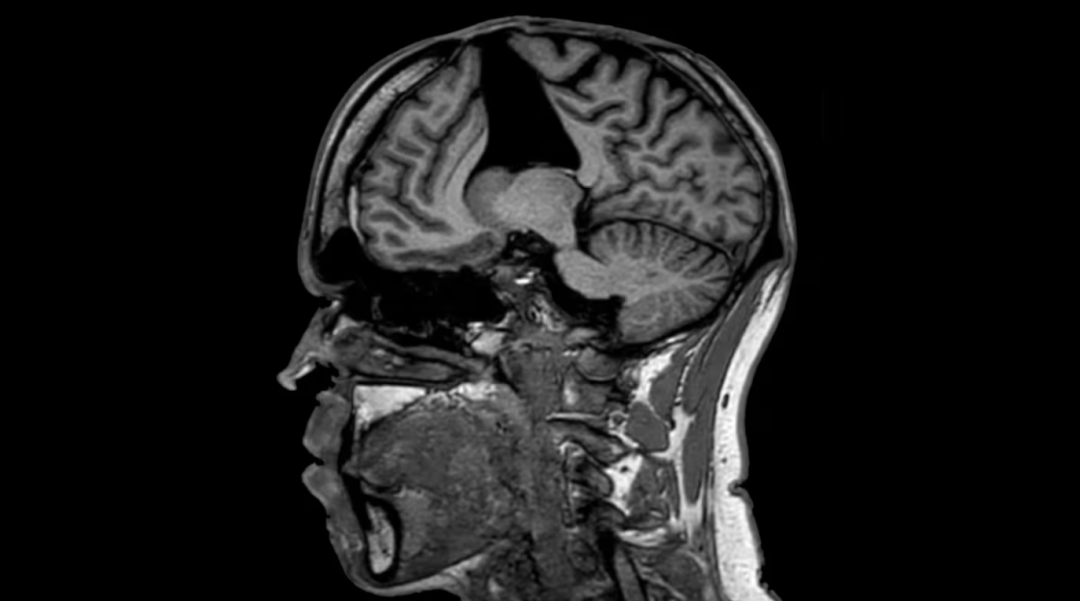

家人带他到医院,经过一系列检查后,医生在他大脑里发现了关键线索:脑部影像提示,他可能患有脑淀粉样血管病(CAA)。

这是一种脑血管疾病,主要是因为一种叫做“β-淀粉样蛋白”的物质在大脑血管壁上异常沉积,导致血管变得脆弱,容易破裂出血,也会引起逐渐加重的认知功能下降——症状表现很像阿尔茨海默病。

医生们开始翻阅他的病史,终于追溯到他在婴儿时期的那次硬脑膜移植手术,并得出了诊断——医源性脑淀粉样血管病(iCAA)。